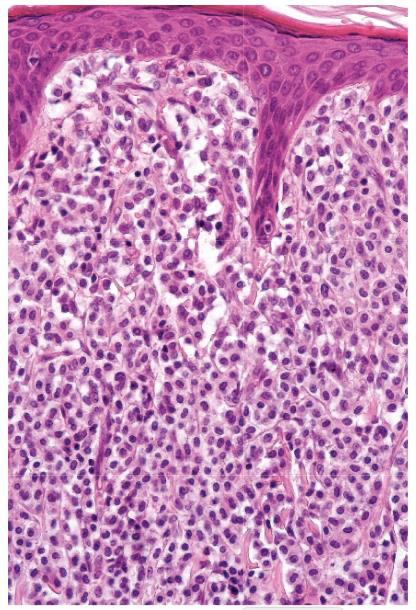

A

CATAGEN follicles are notable by their eosinophilic “glassy” membrane & lack of a hair shaft